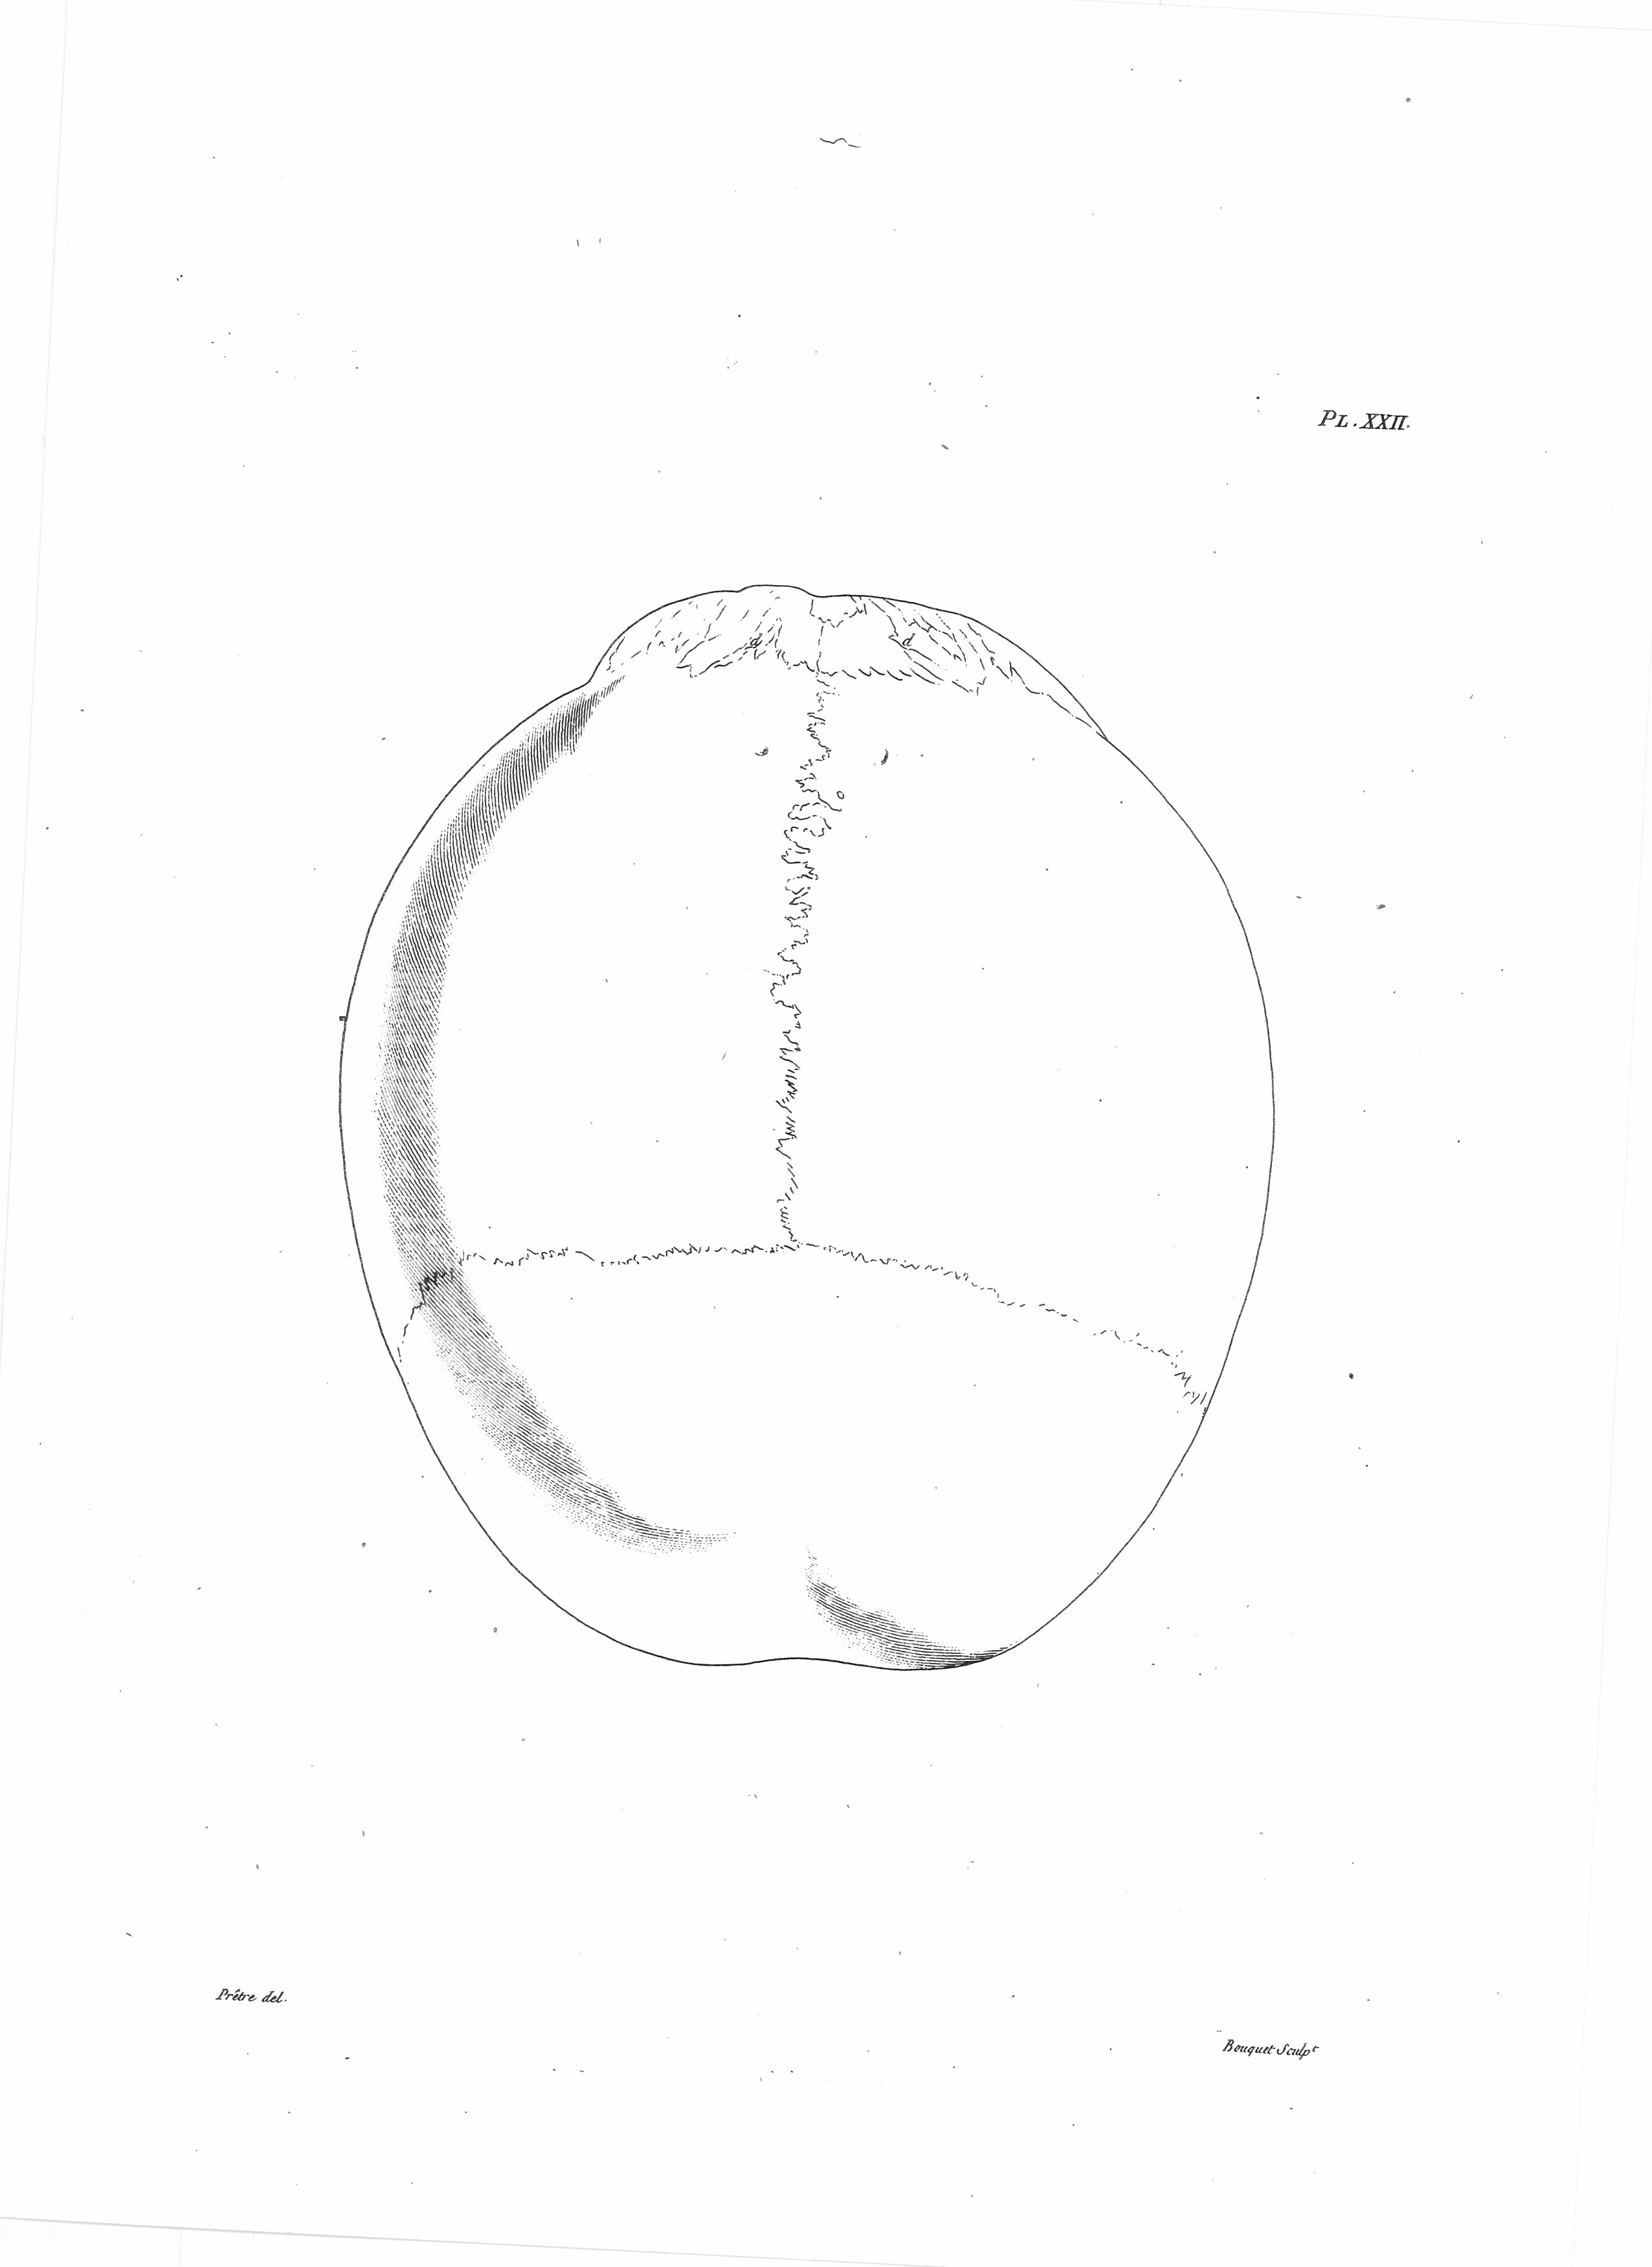

Gall: Plates

Gall, F. J. (1818). Anatomie et physiologie du système nerveux en général, et du cerveau en particulier, Avec des observations sur la possibilité de reconnoître plusieurs dispositions intellectuelles et morales de l´homme et des animaux, par la configuration de leurs têtes.

Librairie Grecque-Latine-Allemande, Vol. 3, I-XXXV u. 1-379 100 planches.